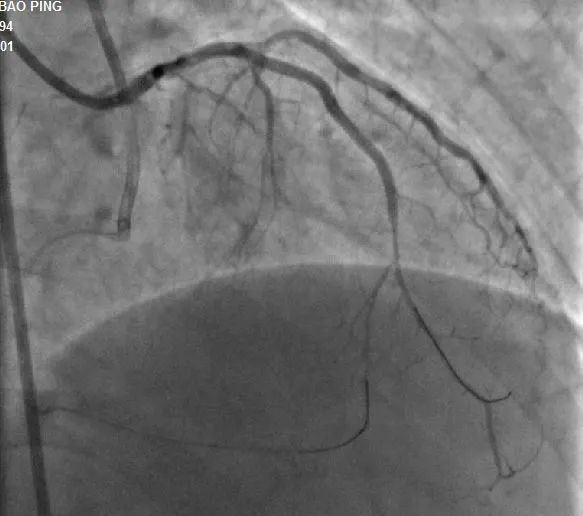

近日 长治二院心血管内科团队 成功完成 一例高难度 逆向CTO(冠状动脉慢性完全闭塞病变)介入手术 该项技术的成功突破 标志着医院心血管内科 冠脉介入技术跃 上了一个新的台阶 ...... 病例分析 手术现场 手术过程:7F LA1.0指引导管到位RCA开口,SionBlue(0.014”、0.5g)导丝送至后降支(PD3 )作为逆向导丝进入间隔支,以tip-injection技术进行间隔支超选择性造影,以明确逆向通路走形。逆行进入LAD中段,再次以tip-injection技术进行超选择性造影以明确LDA闭塞段以远情况,操纵导丝逆向行进至LAD中段闭塞段以远,尝试穿过闭塞段逆行到达LAD近段,推送逆向微导管通过闭塞段进入正向指引导管内,缓慢退出逆向系统至右冠内,逆向造影显示通路安全,撤出逆向系统。顺利预处理闭塞段病变后,于LAD近中段植入两枚支架,优化支架后,结果满意。 ▲术前造影结果 ▲术中逆向通道建立 ▲前降支CTO顺利开通 科室推荐 专家推荐 山西省心脏重症专业委员会常委、心律失常学组常委、介入学组常委。长治市心血管专业委员会、胸痛专业委员会及介入质控部副主任委员。 咨询热线 长治二院心血管内科 0355—3126031 冯翠萍主任 18603550120 姬小飞副主任 15635585652 李晋创医生 13546516641 供 稿丨冯翠萍 李晋创 编 辑丨卞 晨 审 核丨雷 赫